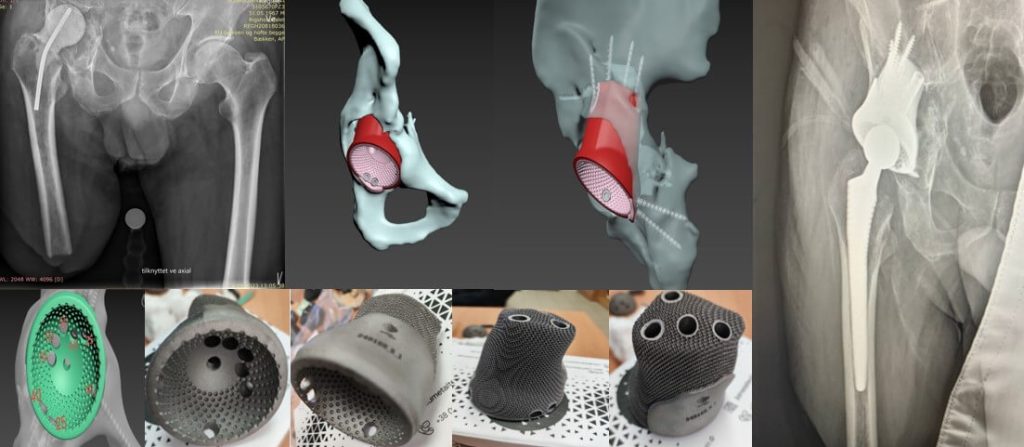

Приклад заміщення дефектів кісток тазу при ураженні пухлиною. Складне індивідуальне ендопротезування кульшового суглоба

Хвора К.,67 років.У 2020 році виконано ТЕП правого кульшового суглобу у зв’язку з діагнозом “Правобічний коксартроз IV ст.” У січні 2022 року хвора госпіталізована в ВЛШМД з діагнозом “вивих ендопротезу”.Проведена ревізія-заміна ацетабулярного компонента та голівки ніжки ендопротезу. Після оперативного втручання у хворої з’явились ознаки інфекції,утворилась нориця.Пройшла консервативне лікування-ефект відсутній. У березні 2023 році хвора повторно госпіталізується у ВЛШМД з діагнозом “вивих ендопротезу” . Проведена повторна ревізія-заміна ацетабулярного компоненту, пластика цементом та гвинтами. В умовах лабораторії біомедичної інженерії ІТО НАМНУ проведено виготовлення та встановлення індивідуальної ацетабулярної западини.

Пацієнтка П. 62 роки звернулася з діагнозом: Двобічний диспластичний коксартроз 4 ст. Стан після коригуючої остеотомії тазу 1984р. Стан після ТЕП лівого кульшового суглоба (2008) та правого кульшового суглоба (2009). Глибока перипротезна інфекція лівого кульшового суглоба. Стан після спейсерування лівого кульшового суглоба (26.09.23). ФНЕ лівого кульшового суглоба 3 ст.

Пацієнтка П. 62 роки звернулася з діагнозом: Двобічний диспластичний коксартроз 4 ст. Стан після коригуючої остеотомії тазу 1984р. Стан після ТЕП лівого кульшового суглоба (2008) та правого кульшового суглоба (2009). Глибока перипротезна інфекція лівого кульшового суглоба. Стан після спейсерування лівого кульшового суглоба (26.09.23) .ФНЕ лівого кульшового суглоба 3 ст.

Пацієнт C. 52 роки звернулася з діагнозом: Наслідки вогнепального поранення. Гнійний артрит правого кульшового суглоба. Спейсер. Значні дефекти правої кульшової западини. Імпрегновано сріблом.